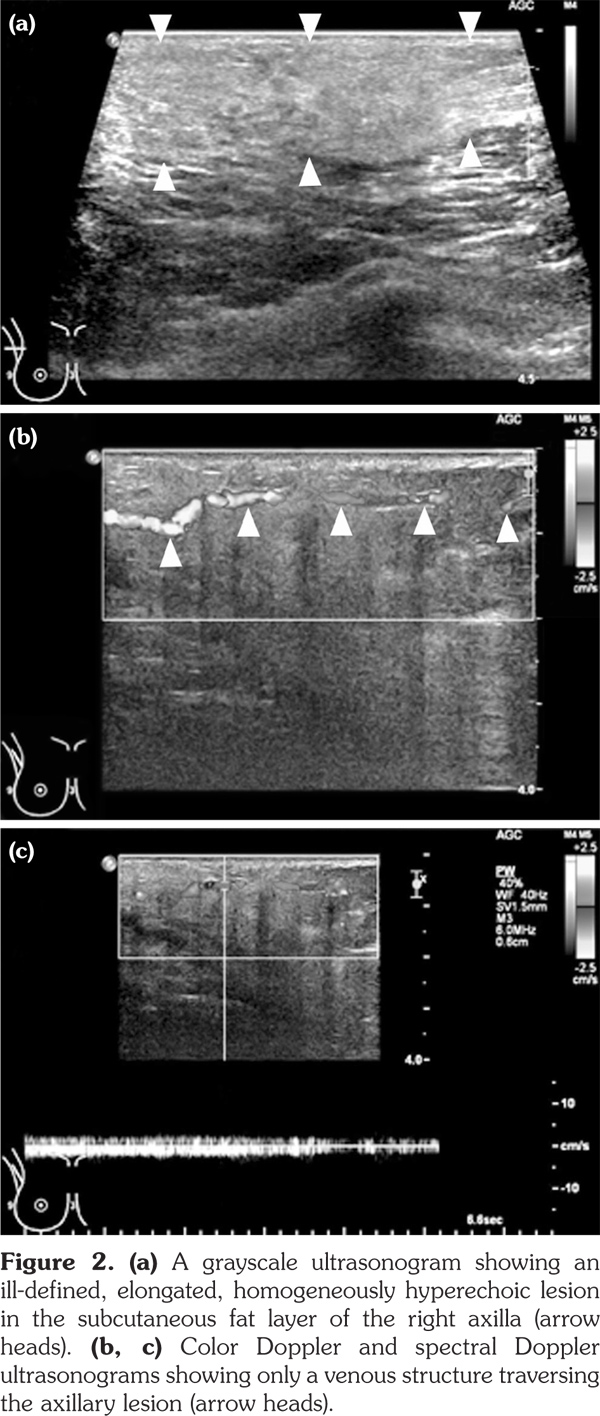

Full-field digital mammography was performed (MAMMOMAT Inspiration; Siemens AG, Munich, Germany). A right mediolateral oblique view revealed an asymmetric density in the right axilla (Figure 1). Ultrasonography was performed with a 5- to 12-MHz linear transducer (iU22; Philips Medical Systems, Bothell, WA, USA), which identified a poorly defined, elongated, homogeneously hyperechoic lesion in the subcutaneous fat layer of the right axilla (Figure 2). The lesion did not exhibit increased vascularity, except for a normal traversing venous structure (Figure 2). The lesion was surgically excised. Pathological examination confirmed the diagnosis as lipogranuloma (Figure 3). On the other hand, complete blood test results were normal.

In the breast, lipogranulomas have been reported after the release of the silicone gel from breast implants, after the application of a traumatic treatment called “Bu-Hwang,” and after phenothiazine therapy.(8,9) The mammographic features of lipogranuloma have been described in only two cases. These cases presented a bizarre-shaped lesion with bright density which proved to be lipogranuloma with osseous metaplasia and an irregular mass containing several microcalcifications.(8,10) The ultrasonographic features of breast lipogranuloma have been described in only one case, which presented an ill-defined hyperechoic lesion.(10)